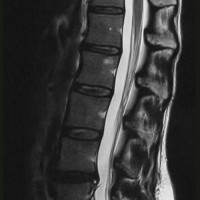

A free medical education seminar series for everyoneA FREE spine education seminar series for everyone Back pain has many faces and to many people it can be distressing, disabling or even frightening. Whether back pain comes from a strain, degenerative disc disease, a herniated disc, spinal stenosis, spondylolisthesis, a complex deformity or even a fracture, there are many options that can help you to live an active lifestyle. Additionally, osteoporosis is another disease that you may not even know you have. Learn from these dynamic experts about the various types of back problems and the latest treatments available. We will discuss the problems, the solutions and leave time for your questions to help you be active. Talk with the experts and get your concerns addressed. Spine Program